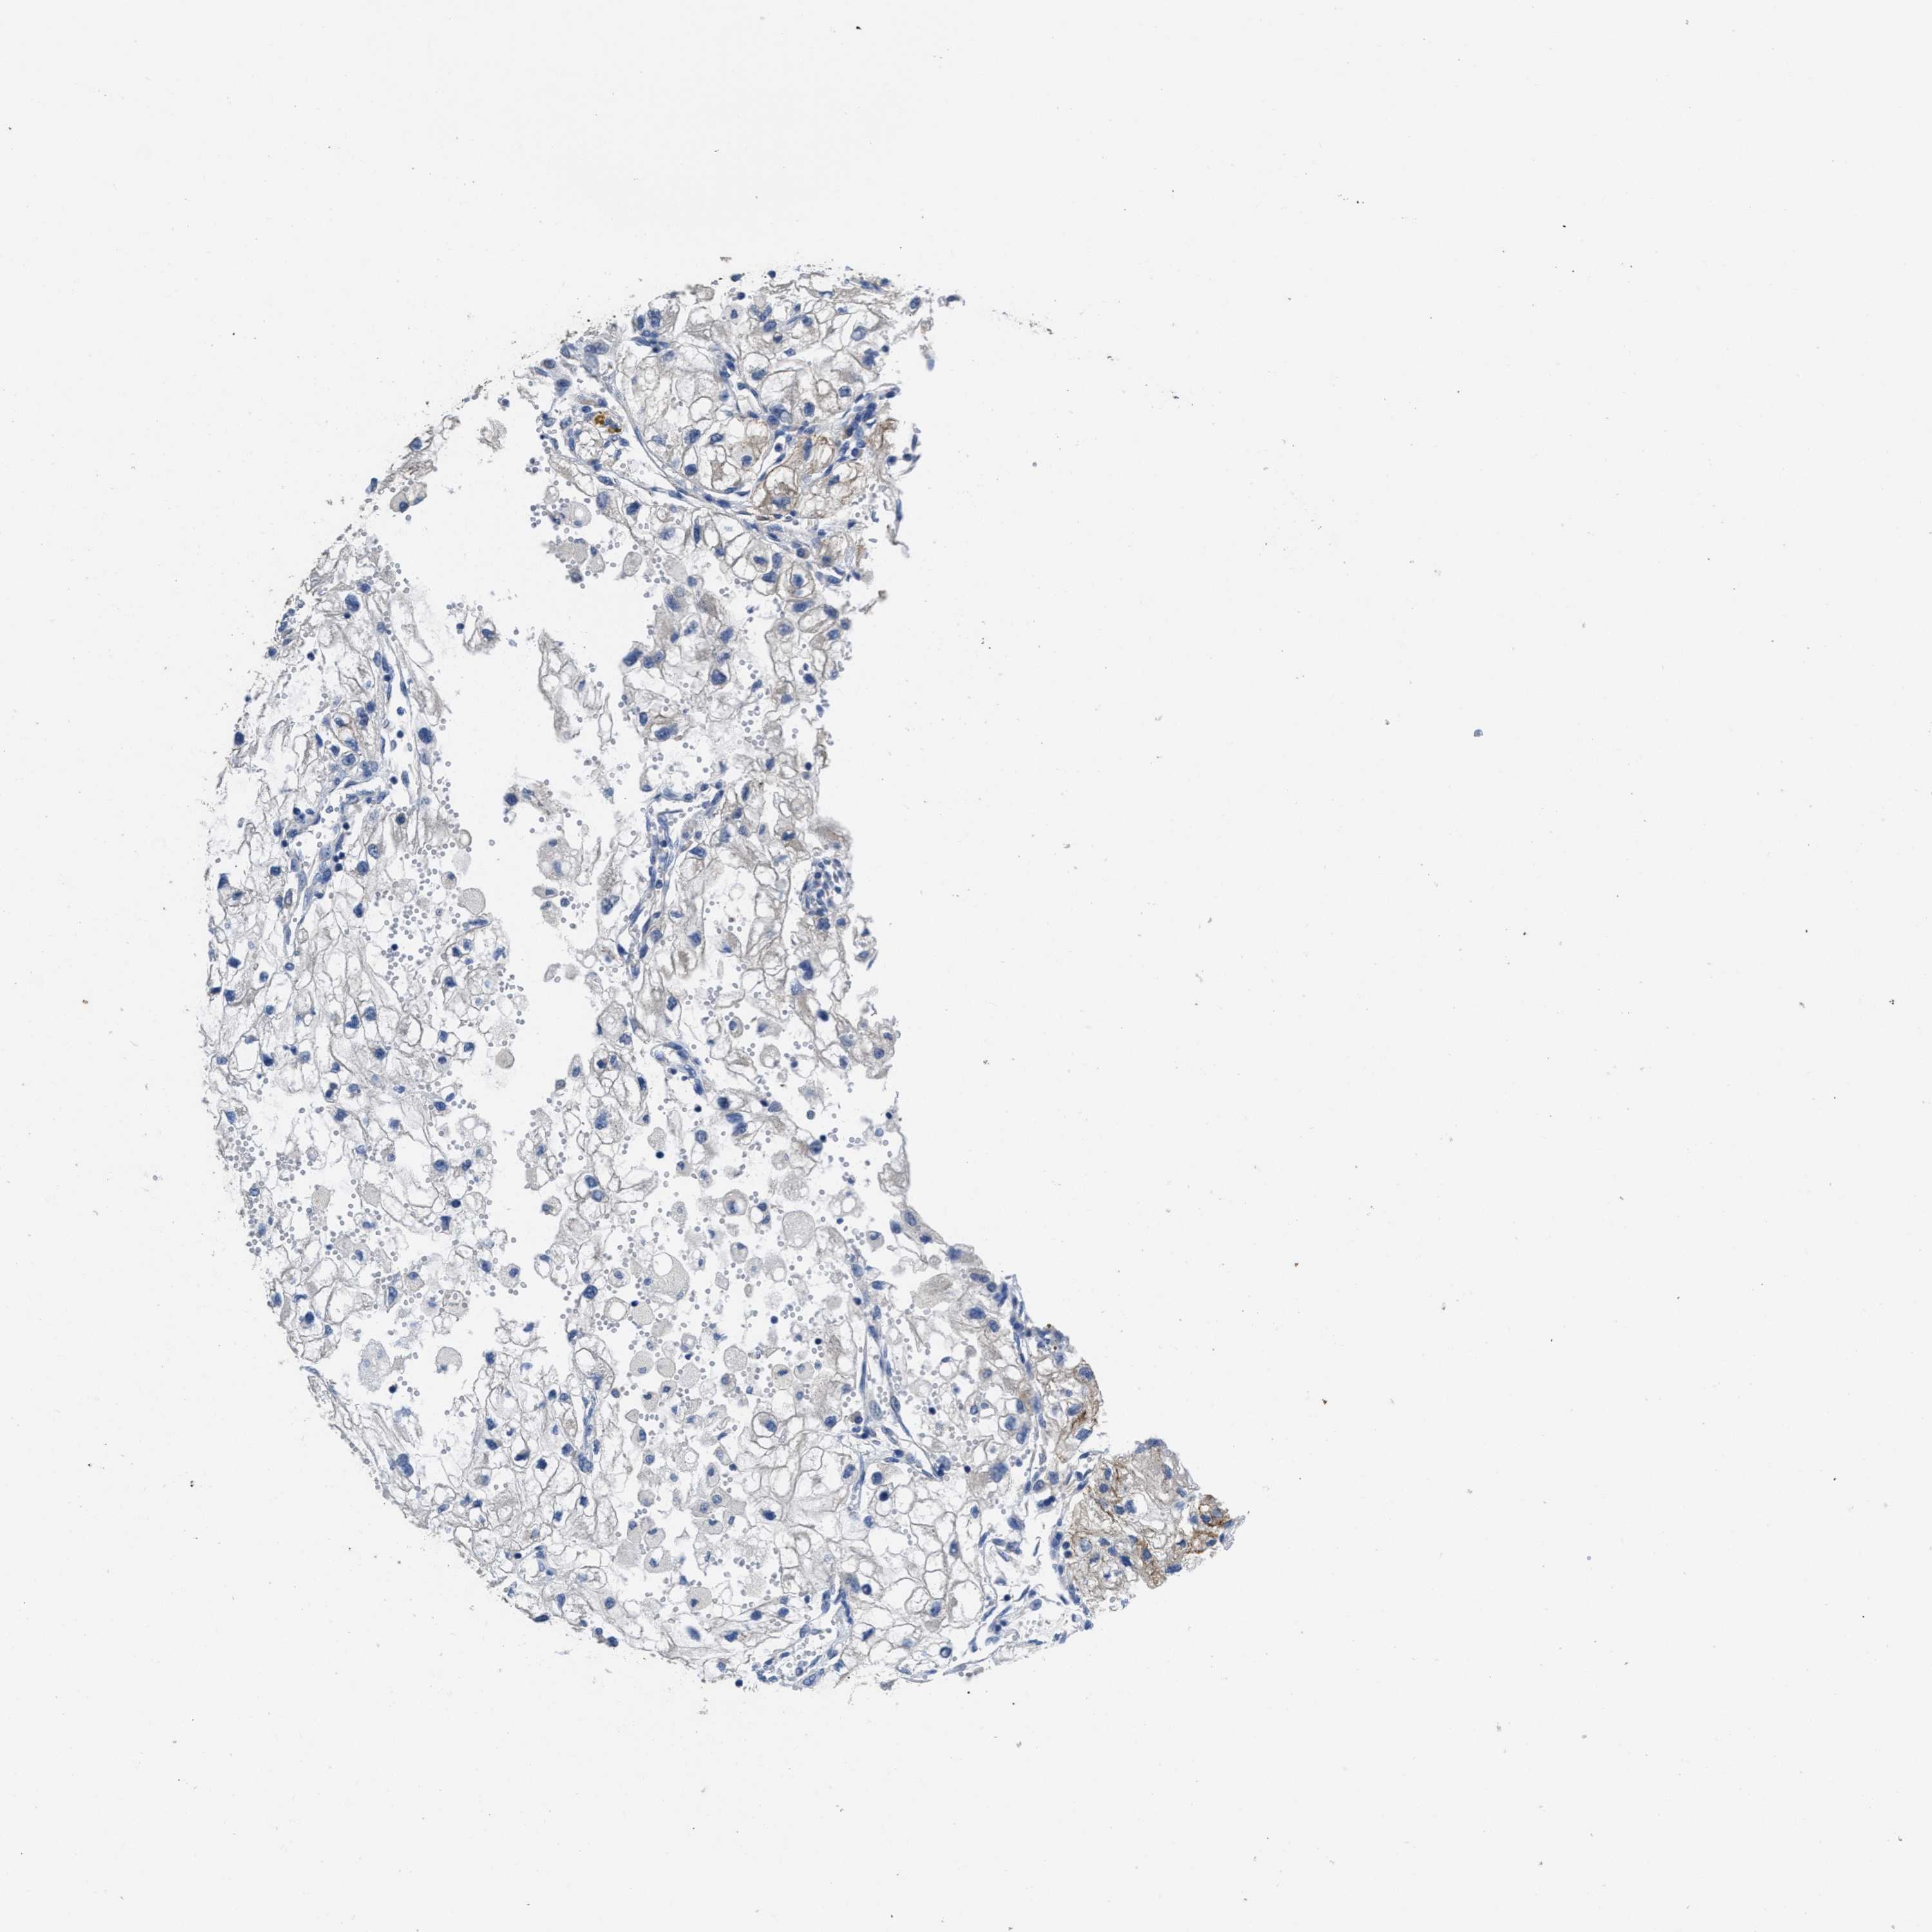

CANCER RENAL CANCER Show tissue menu

KICH TCGA KIRC TCGA KIRC VALIDATION KIRP TCGA PROTEIN RCC CPTAC PROTEIN EXPRESSION